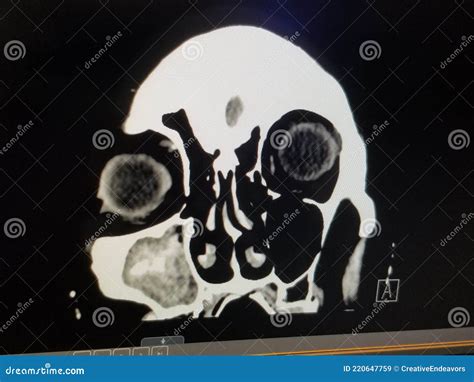

A computed tomography (CT) scan is a sophisticated imaging technique that uses X-ray technology coupled with computer processing to create highly detailed, multi-dimensional images of the body. When specifically applied to the sinuses—often referred to as a paranasal sinus CT—the procedure captures images of the air-filled cavities located around the nose and eyes.

Unlike standard X-rays, which may offer a limited view, a Ct scan sinus evaluation provides a "slice-by-slice" perspective. This allows an Ear, Nose, and Throat (ENT) specialist to detect subtle abnormalities that might be hidden during a routine physical examination. It helps in distinguishing between simple inflammation, polyps, fungal infections, or structural issues like a deviated septum.

• Map Anatomical Variations: Everyone’s sinus anatomy is unique. Before surgery, surgeons need to see the exact layout to avoid damaging critical structures like the eye socket or the base of the skull.